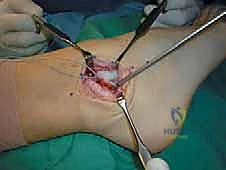

الخطوة الثانية: الشق الجراحي والوصول للأربطة

يقوم أ.د. محمد هطيف بعمل شق جراحي صغير ودقيق (حوالي 4-5 سم) على شكل حرف J أو شق منحني خلف وأسفل العظمة البارزة في الكاحل (Lateral Malleolus). يتم استخدام تقنيات الجراحة الميكروسكوبية للحفاظ على الأعصاب السطحية (مثل العصب الشظوي السطحي) والأوعية الدموية الدقيقة.